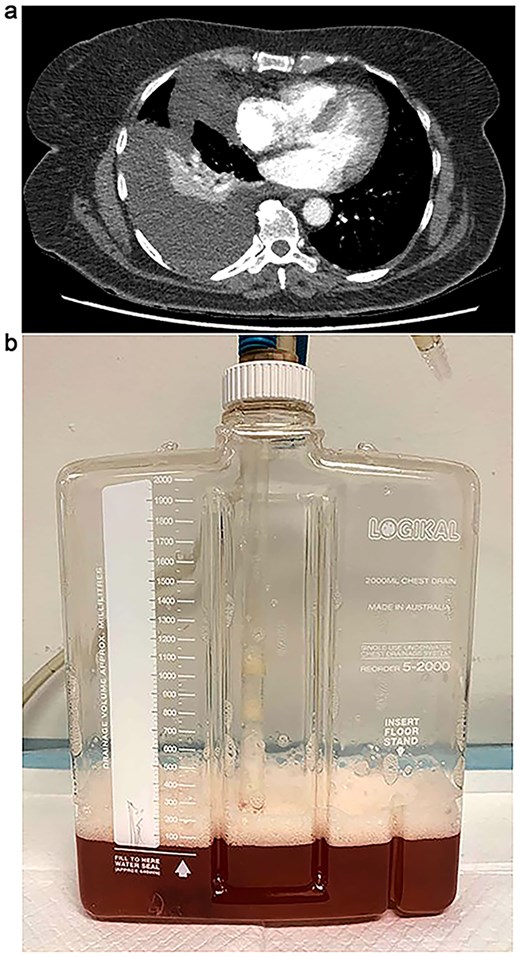

On postoperative day 10, a bile leak was suspected due to high-volume hepatic drain output of dark brown fluid. However, an initial computed tomography (CT) cholangiogram failed to identify a source of the leak. By day 20, the patient developed worsening exertional dyspnoea and orthopnoea. A CT pulmonary angiogram ruled out pulmonary embolism but revealed a right-sided pleural effusion with compressive atelectasis in the right lower lobe (Fig. 1a). She was treated with intravenous diuretics, physiotherapy, and incentive spirometry.

(a) CT chest demonstrating progressive large right-sided pleural effusion with new loculation and compressive right lower lobe collapse. (b) Bilious pleural fluid with froth following ultrasound guided intercostal pigtail catheter insertion.

Due to further respiratory deterioration, repeat imaging was performed and showed an increase in the right pleural effusion with new loculation (Fig. 1a). An ultrasound-guided pigtail drain was inserted, and analysis of the turbid bilious pleural fluid confirmed bilothorax with an elevated pleural fluid to serum (PF/S) bilirubin ratio of 7.6 (Fig. 1b). There were no malignant cells or microorganisms in the fluid. Broad-spectrum antibiotics were started for potential respiratory and intra-abdominal sepsis. A follow-up chest radiograph 4 days after thoracentesis showed near-complete resolution of the effusion. The patient was discharged on day 30 postoperatively and remained well, with no symptom recurrence at her 1-month follow-up.